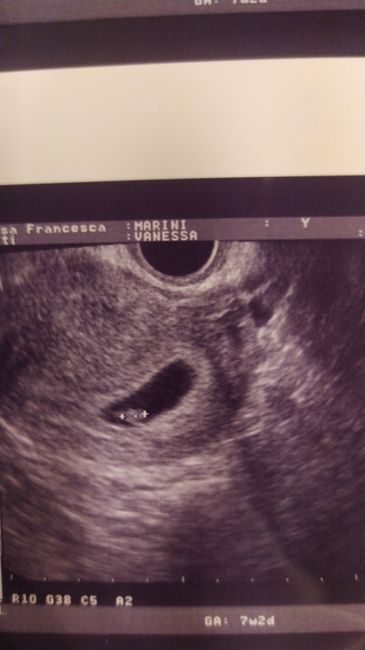

Ho caricato una foto nel post di Vanessa

1660 giorni fa

Chi ne capisce un po' meglio di me? Che vi sembra? Se la posiziono sulla pancia sta a sinistra...